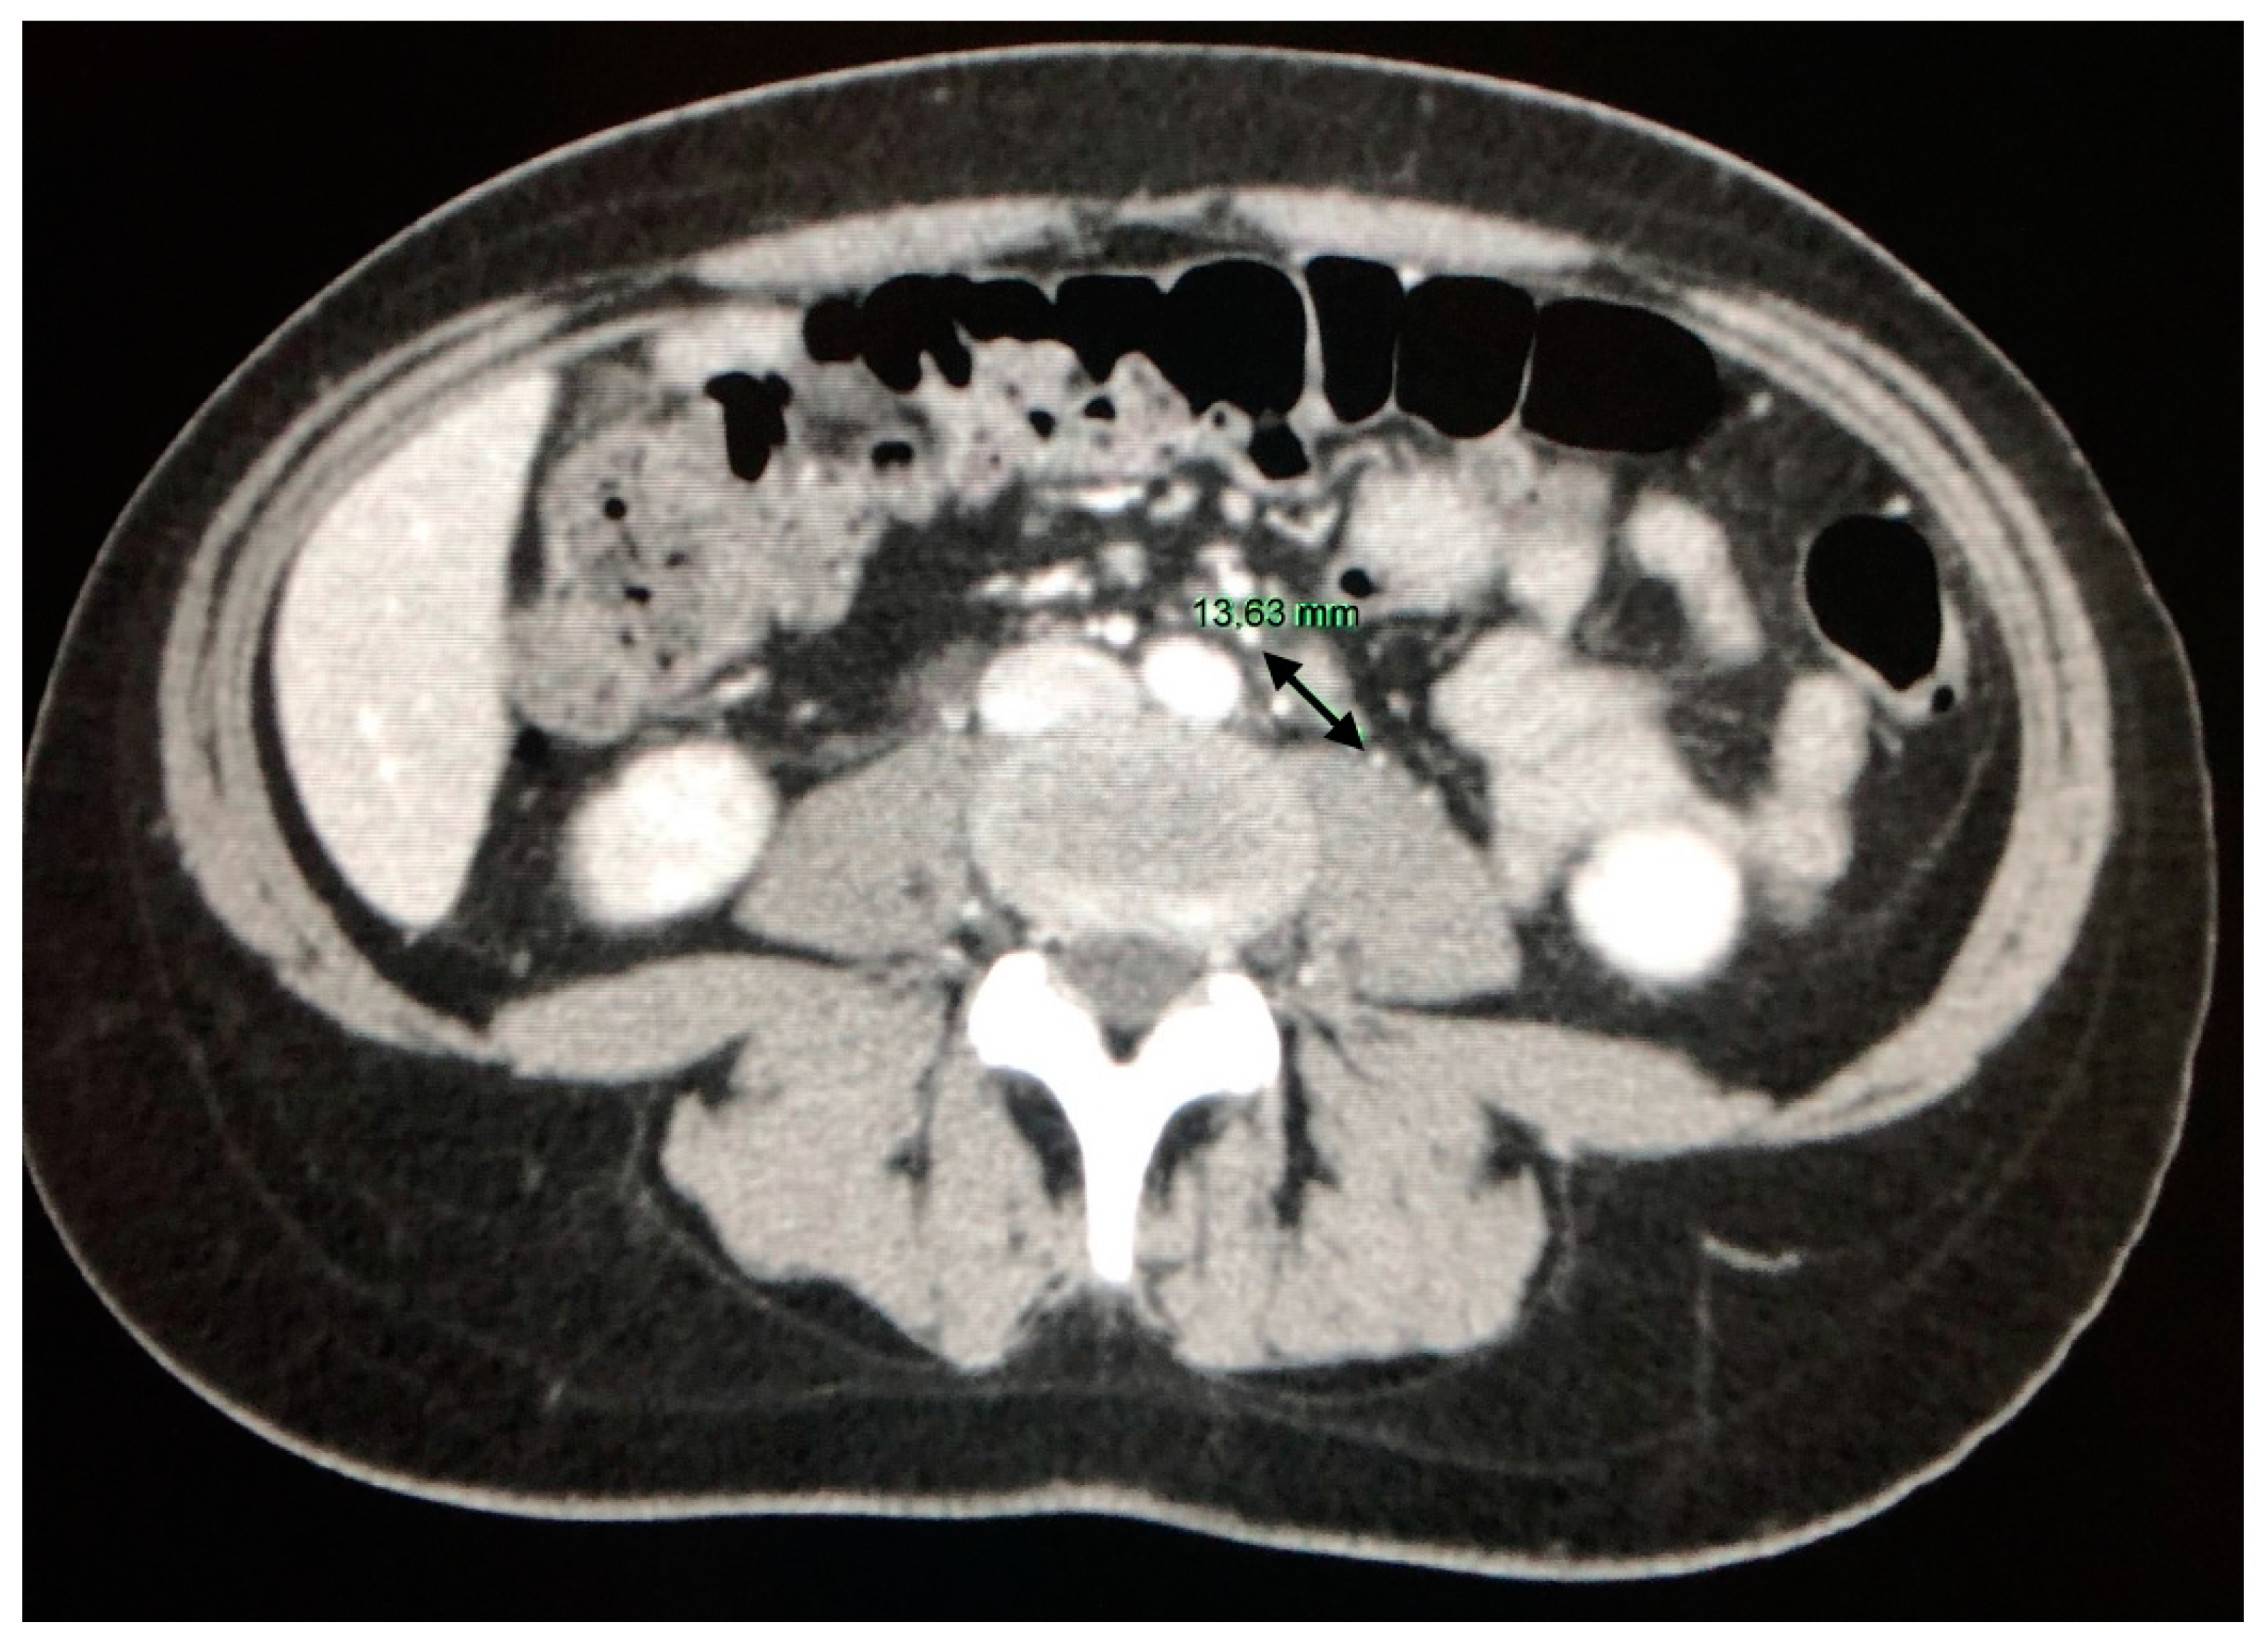

4.1. The Involvement of Liver, Spleen and Abdominal Lymph Nodes

- Gezer, N.S.; Başara, I.; Altay, C.; Harman, M.; Rocher, L.; Karabulut, N.; Seçil, M. Abdominal sarcoidosis: Cross-sectional imaging findings. Diagn Interv. Radiol. 2015, 21, 111–117. [Google Scholar] [CrossRef]

- Warshauer, D.M.; Lee, J.K.T. Imaging Manifestations of Abdominal Sarcoidosis. Am. J. Roentgenol. 2004, 182, 15–28. [Google Scholar] [CrossRef]

- Folz, S.J.; Johnson, C.D.; Swensen, S.J. Abdominal Manifestations of Sarcoidosis in CT Studies. J. Comput. Assist. Tomogr. 1995, 19, 573–579. [Google Scholar] [CrossRef] [PubMed]